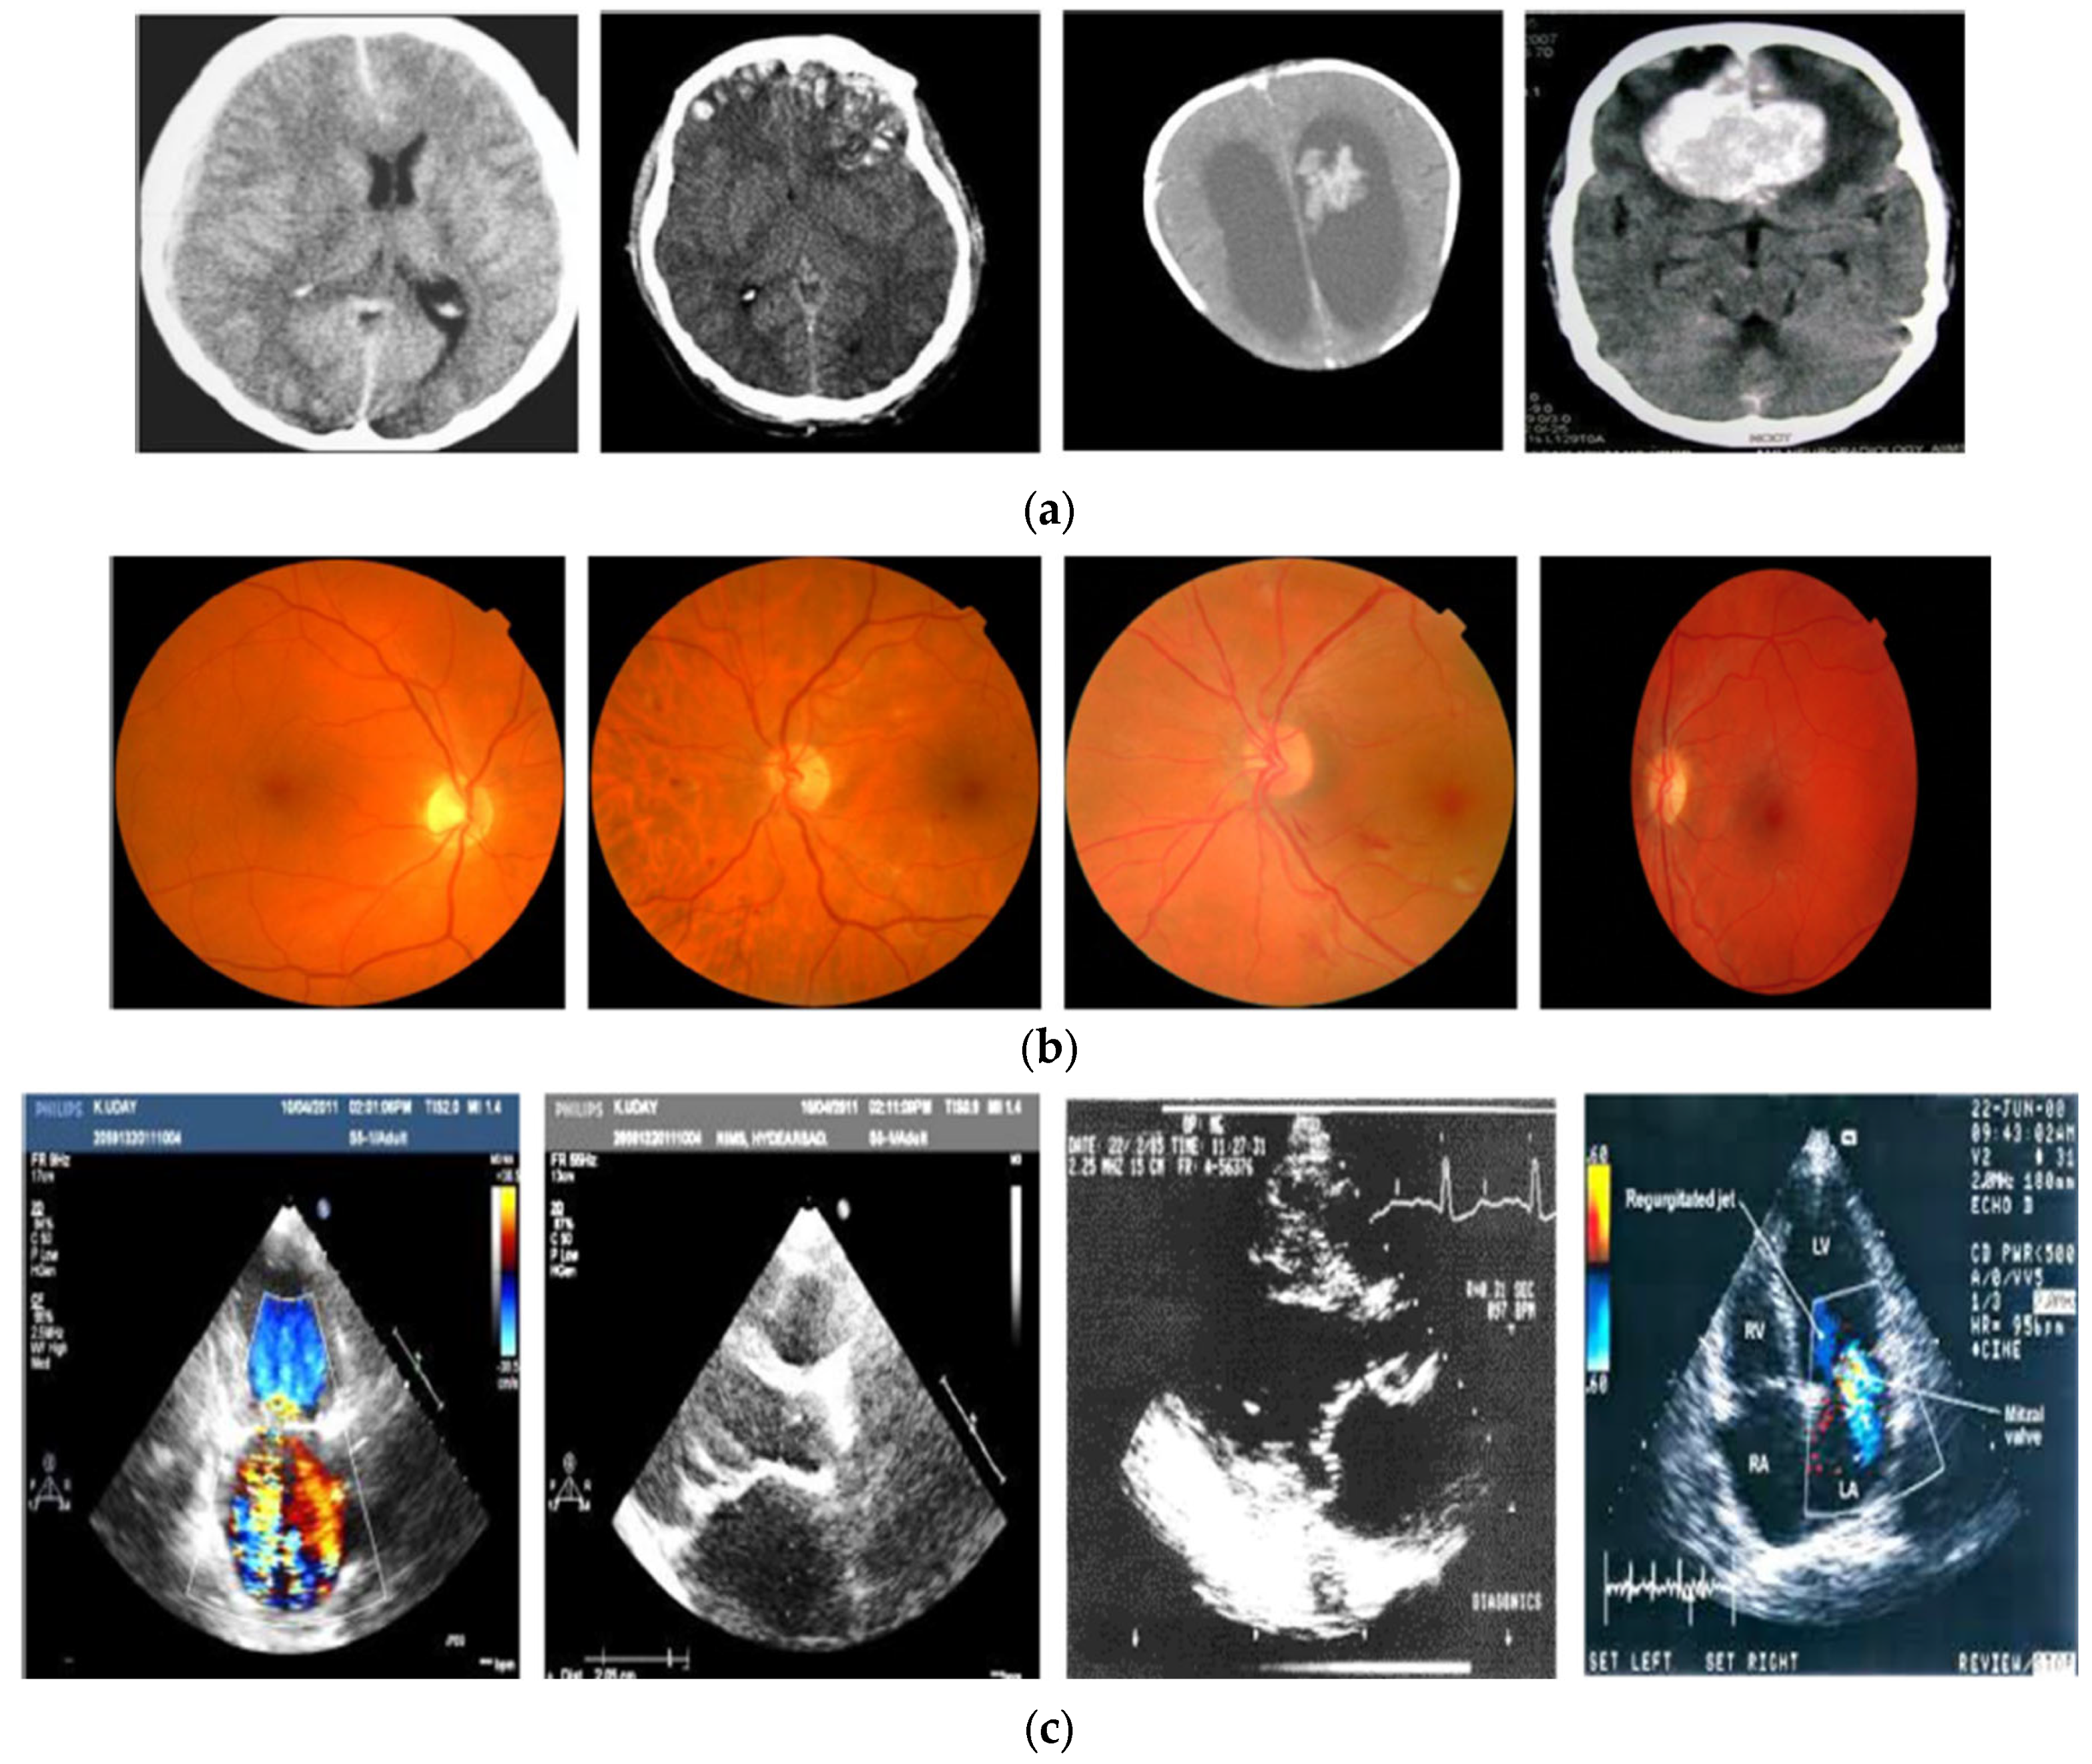

| Images | Encrypted Image | PSNR | MSE | BER | SSI | CC |

|---|---|---|---|---|---|---|

![]() | ![]() | 59.23 | 0.12 | 0 | 1 | 0.95 |

![]() | ![]() | 58.22 | 0.09 | 0 | 1 | 1 |

![]() | ![]() | 59.34 | 0.15 | 0.01 | 1 | 0.98 |

![]() | ![]() | 63.25 | 0.10 | 0 | 0.01 | 0.96 |

![]() | ![]() | 59.64 | 0.12 | 0.98 | 0.02 | 0.97 |

![]() | ![]() | 60.36 | 0.11 | 1 | 0 | 1 |